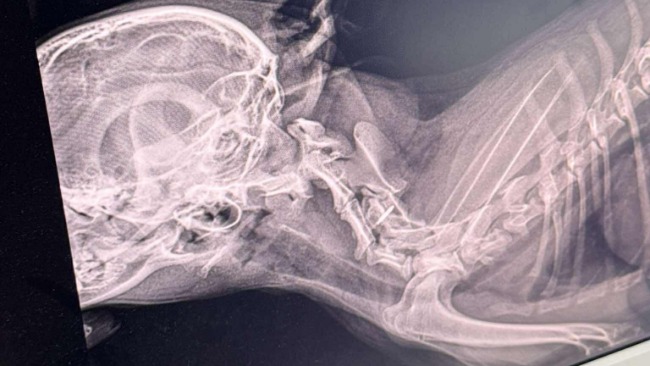

Dostaliśmy wyniki tomografu naszej podopiecznej Wiktorii… i niestety – nie są dobre.

Diagnoza: niestabilność szczytowo-obrotowa z podwichnięciem obrotnika C2, co powoduje ucisk na rdzeń kręgowy. To właśnie dlatego Wiktoria nie potrafi normalnie chodzić. Każdy krok to ogromny wysiłek i zagrożenie – może dojść do pogłębienia urazu, a w najgorszym przypadku – do trwałego paraliżu.

Dalsza poprawa jest niemożliwa bez neurochirurgicznej interwencji.Lekarze stwierdzili niedowład kończyn piersiowych, bardziej nasilony po prawej stronie – wszystko wskazuje na ucisk w odcinku szyjnym rdzenia kręgowego.